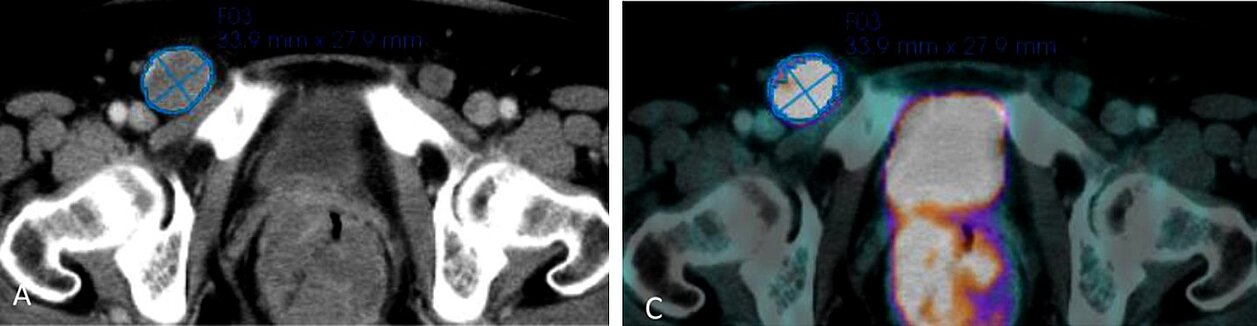

Gegenwärtig liefert das 18F-FDG-PET/CT die genauesten Ergebnisse für das Staging, das Follow-Up und die präoperative Beurteilung von Patienten mit fortgeschrittenem Melanom. Dennoch hat sich die CT-Texturanalyse als nützlich für die Gewebecharakterisierung, für die Vorhersage des Mutationsstatus und der Patientenprognose in der onkologischen Bildgebung bei verschiedenen Tumorentitäten erwiesen.

Es wurden Datensätze von 66 Patienten mit einer Metastase (53 Patienten) oder mehreren Metastasen (13 Patienten) ausgewertet. mint Lesion™ wurde verwendet, um die größte Metastase bei jedem Patienten zu beurteilen und folgende Parameter zu extrahieren:

- CT-Texturparameter (Dichte, Standardabweichung (SD), Kurtosis, Skewness, Mittelwert der positiven Pixel (MPP), Uniformität der Verteilung der positiven Pixel (UPP), Entropie und Uniformität) und

- Semiquantitative 18F-FDG-PET-Parameter (Volumen sowie Mean Standardized Uptake Value (SUVmean) und Peak Standardized Uptake Value (SUVpeak)).